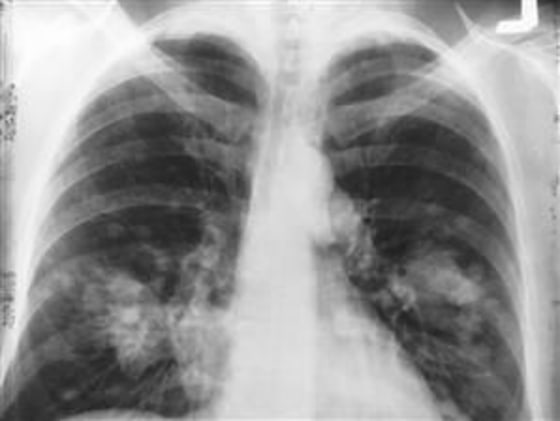

Lung cancer is the No. 1 cancer killer, with 221,200 new cases and 158,000 deaths expected this year in the U.S., according to the National Cancer Institute.